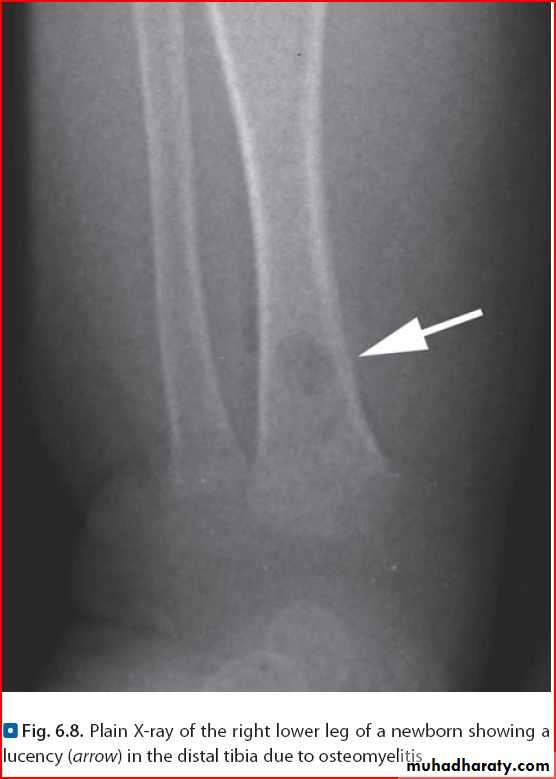

Osteomylitis